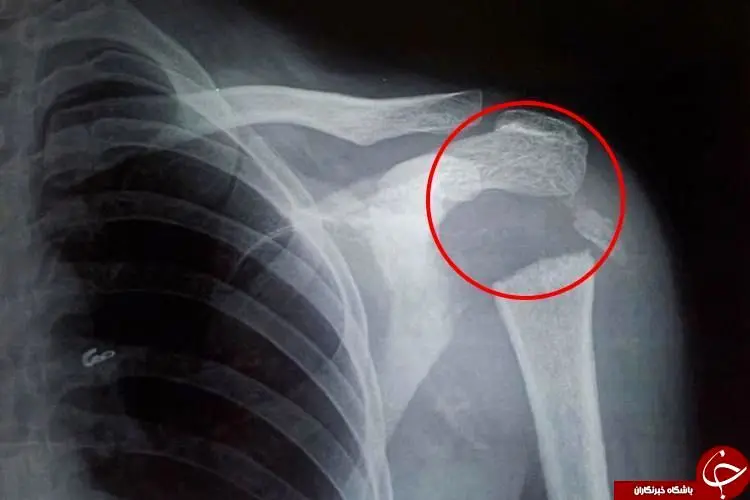

یک زن جوان هندوستانی به علت ناپدید شدن قسمتی از استخوانهای شانهاش قادر است دستش را به حالت 180 درجه بچرخاند.